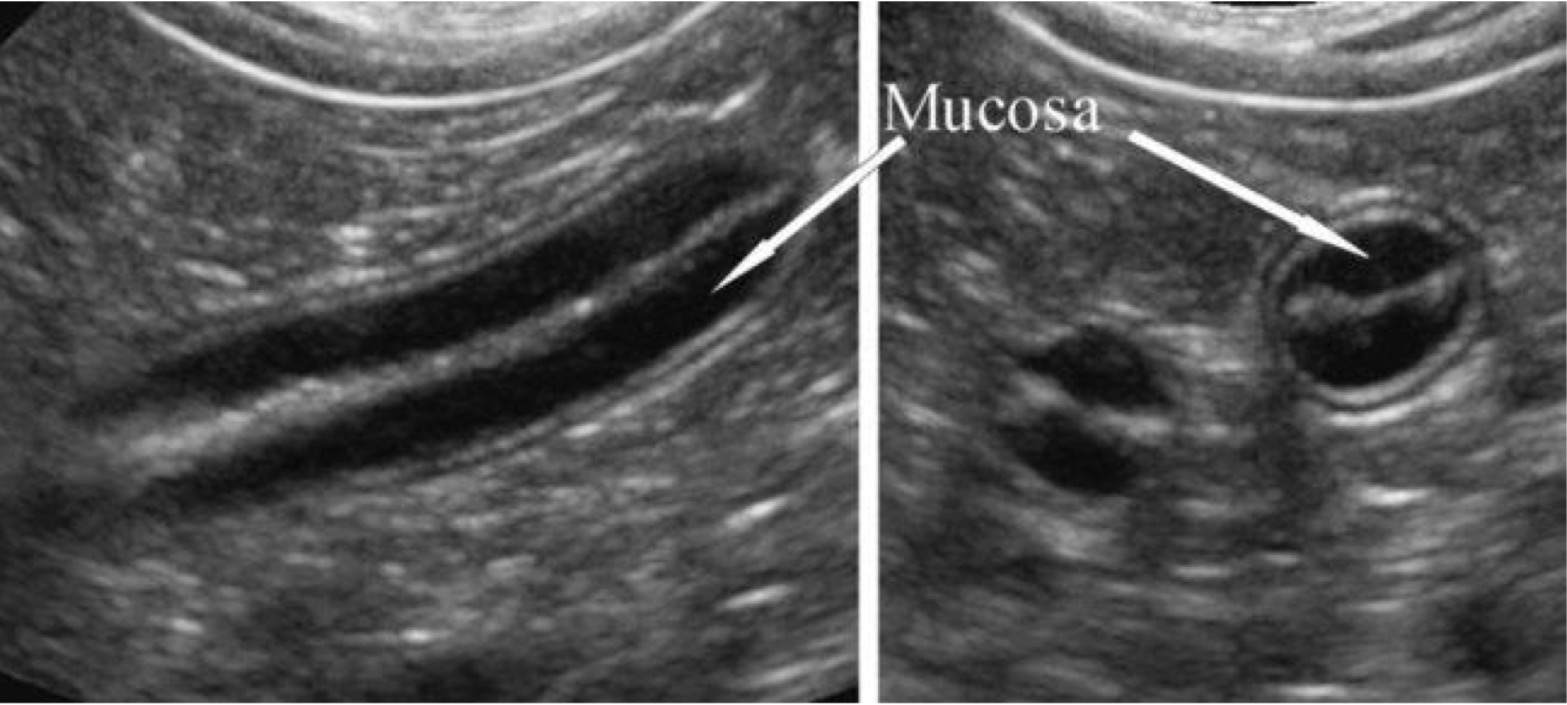

Lumen/mucosa interface -hyper

Mucosa- hypo

Submucosa- hyper

Muscularis- Hypo

Serosa- hyper

When looking at a ultrasound of small intestinal loops, what are the differing layers from center to outer and their echogenicities?

Small intestine

Organ?